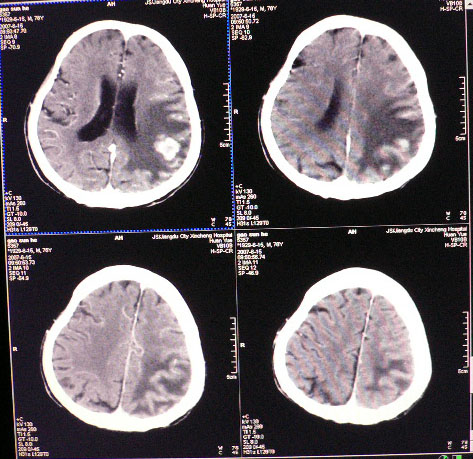

男性,78岁,失语,意识障碍1天

平扫ct值为40-45hu,增强为不均匀强化,ct值为81-85hu

皮层下厚壁花环状高密度影,明火显强化,大范围指样水肿,支持转移瘤诊断。其后上方好像还有小灶。

发生于质下,软组织影,形态不规则,周边大片水肿,明显环状强化,中间低密度液化坏死,建议结合临床

从发病部位,病灶强化特点、周围水肿情况支持脑转移瘤诊断,可进一步检查查找原发灶。